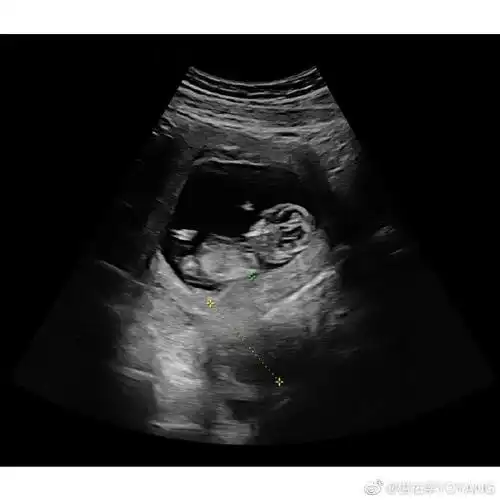

恭喜杨佑宁晒未婚妻照和b超照官宣当爸爸